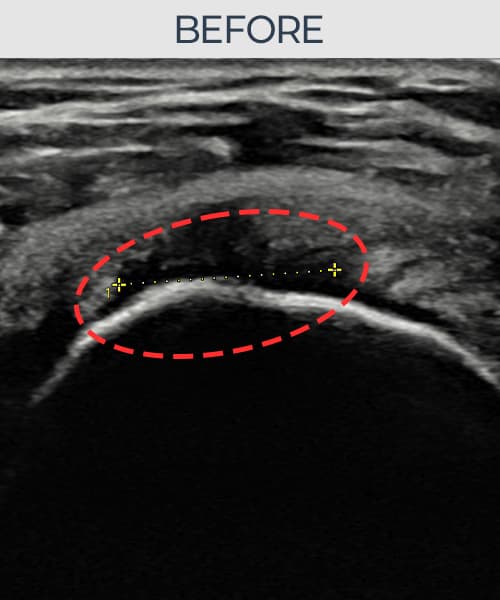

超音波検査にて腱板 関節面側断裂(9mm × 5mm (腱厚の約50%欠損))を確認。縫縮術施行後、腱の連続性が回復し、日常生活に復帰されました。

施術前

術前超音波にて腱板 関節面側断裂・肩棘上筋腱のエコー不連続と腱欠損(9mm × 5mm (腱厚の約50%欠損))を確認。術後超音波では断裂部位が再生組織で充填され、腱の連続性回復とエコーパターンの正常化が確認されました。

持続する肩痛で来院された患者様です。超音波検査にて腱板 関節面側断裂(欠損:9mm × 5mm (腱厚の約50%欠損))を確認し、超音波ガイド下で非手術的縫縮術を施行しました。術後は約4〜6週間のブレース装着の後、段階的なリハビリプログラムを実施。経過超音波で腱の連続性回復を確認し、患者様は無事に日常生活へ復帰されました。